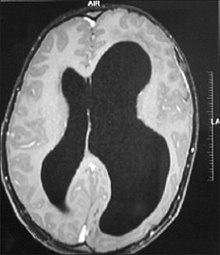

An MRI of a patient with benign familial macrocephaly (male with head circumference > 60 cm)

Benign macrocephaly can occur without reason or be inherited by one or both parents (in which it is considered benign familial macrocephaly and is considered megalencephaly form of macrocephaly). Diagnoses for familial macrocephaly is determined by measuring the head circumference of both parents and comparing it to the child's. Benign and familial macrocephaly is not associated with neurological disorders.[2] While benign and familial macrocephaly does not result in neurological disorders, neurodevelopment will still be assessed.

Although neurological disorders do not occur, temporary symptoms of benign and familial macrocephaly include: developmental delay, epilepsy, and mild hypotonia.[2]